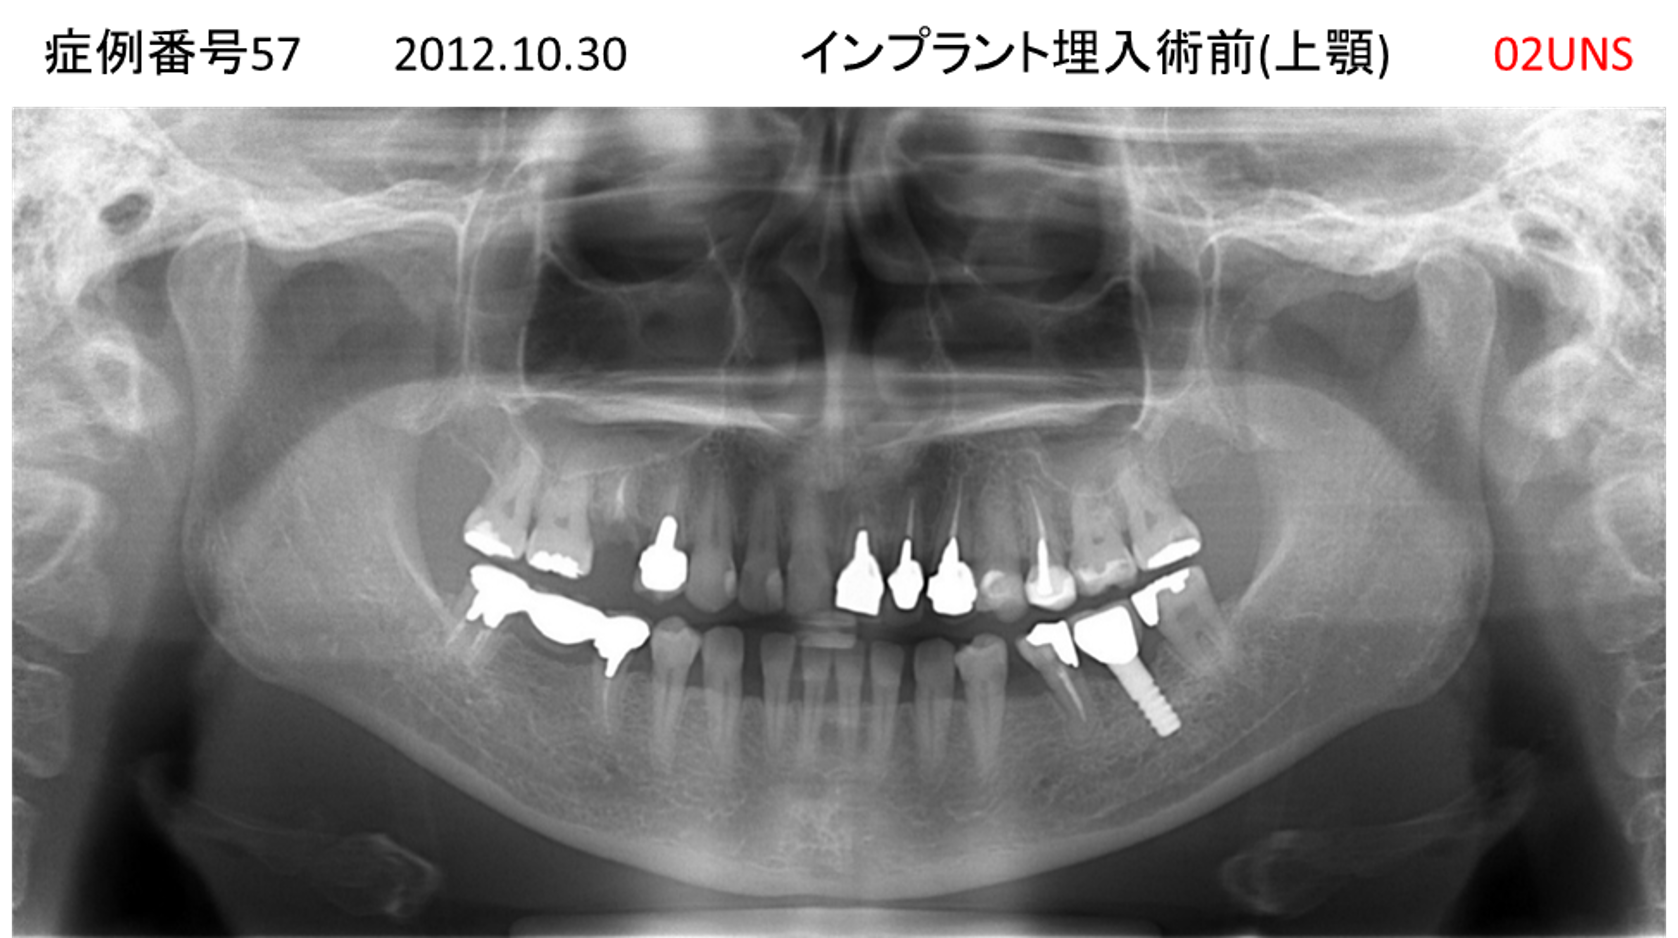

義歯が合わない、噛めない患者様のインプラント症例

| 治療名称 |

インプラントコーヌステレスコープ |

| 治療費用 |

270万円+税 |

| 治療期間 |

4か月 |

| 患者さんの症状(主訴) |

義歯が合わない、噛めない |

| 治療内容 |

インプラント、義歯作製(コーヌステレスコープ) |

| 治療結果 |

しっかり噛めるようになった。見栄えが良くなった。 |

| 治療の注意点(リスク/副作用) |

義歯が壊れた場合、インプラントが壊れた場合は再治療が必要 |